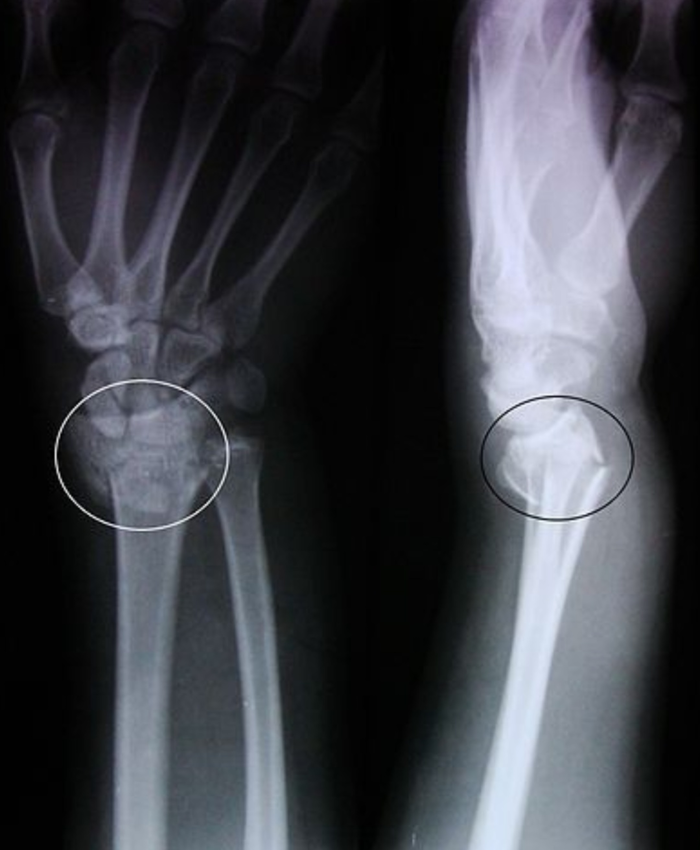

Ну вот и выпал достаточно сильный снегопад . Этой ночью снежок красиво подмерзнет, лужица,переливаясь в лунном свете превратится в лёд... А на утро , как в сказке , бабушка с тросточкой пойдет по делам на рынок ,или девушка на высоченных каблуках попорхает на работу... И к сожалению , кто то из них обязательно попадет к вам на прием. Отсидит очередь , пройдет битву с " мне только спросить" ," я в 6 утра занимал" , " я по талону!" и получит наконец то высококвалифицированную помощь,коллеги)

А ночью, идя на дежурство . Ты точно будешь знать,что после такой замечательной снежной и морозной ночи, твои дежурства запестрят вдвойне от любителей прибухнуть )

В общем, начинается настоящая зима. И мы с Вами,коллеги -травматологи , должны снова латать павших Войнов в этой битве! До скончания веков! В бой!